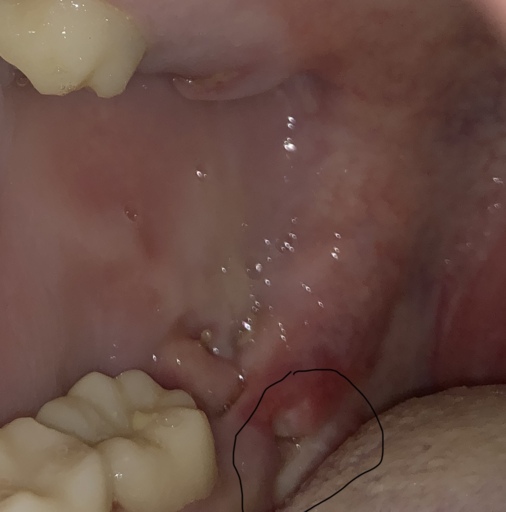

Is this an infection?

I just had all 4 wisdom teeth removed 3 days ago and this is on the bottom left side and I can’t tell what it is. It is only on the left bottom side and from trying to look it up on the internet I can’t tell if it’s an infection or not.